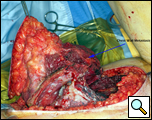

Eleven months later, he presented with a several month history of a painful fixed, firm mass over the pectoral area of the left chest and a smaller mass inferior to this (Figure 1). CT scan demonstrated a new 2 cm nodule in the left upper lobe associated with an anterior chest wall mass six centimeters in size in addition to bilateral new pulmonary nodules (Figure 2). The mass was tethered to the skin and in danger of eroding through it. The patient underwent en-bloc resection of the chest wall and adjacent lung (Figures 3a-c). The resulting defect (Figure 4a) was reconstructed with 2 mm Gore-Tex patch (Figure 4b) and pectoralis major muscle flap (Figure 4c) with primary skin closure (Figure 4d). The pathology revealed metastatic chordoma (Figures 5a-d). The patient recovered well, leaving the hospital on the sixth postoperative day.